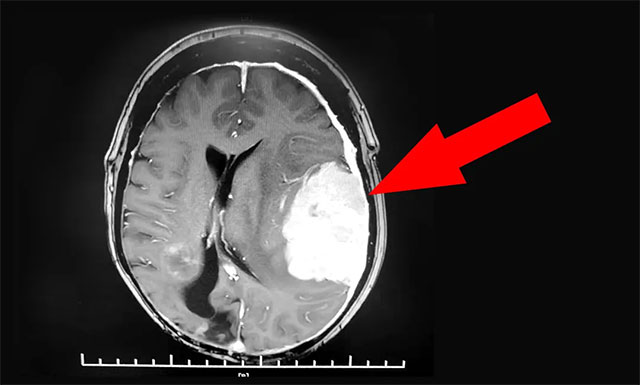

▲ 患者左側(cè)顳頂葉巨大占位

經(jīng)外院檢查,發(fā)現(xiàn)患者左側(cè)顳頂葉占位予以保守治療。半年后患者病情進一步加重,復(fù)查發(fā)現(xiàn)占位區(qū)域水腫較前進展,中線發(fā)生明顯偏移,腦組織受壓程度嚴(yán)重,隨時可能出現(xiàn)危及生命的腦疝,病情十分危重。

沈建康教授團隊首先為患者進一步完善檢查,頭顱MRI增強檢查顯示,患者左側(cè)顳頂葉部位的腫瘤約為6.3cm×4.4cm×6.7cm,體積巨大。經(jīng)行DSA檢查發(fā)現(xiàn),腫瘤包裹纏繞多根重要的動脈血管,血供非常豐富。盡管切除難度高,手術(shù)風(fēng)險大,但綜合分析考慮腫瘤為腦膜瘤,系良性腫瘤,手術(shù)成功可以治療好。